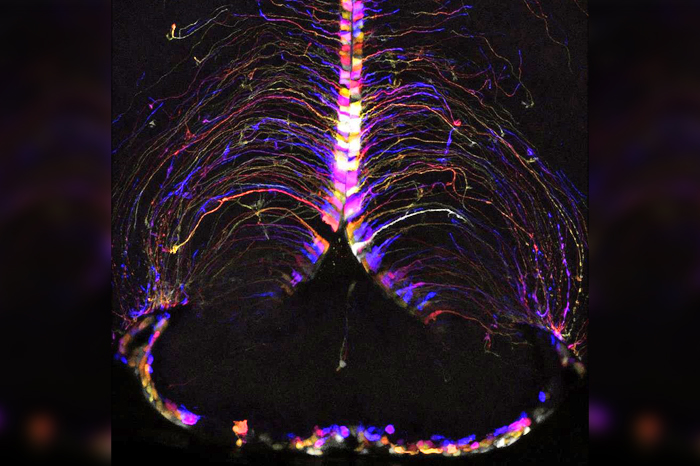

Los hallazgos, descritos en la revista Nature, son fruto del mapeo genético de más de 1.2 millones de células de 16 regiones del cerebro de ratones jóvenes (de dos meses) y viejos (de 18 meses), en el marco de la ambiciosa iniciativa de investigación cerebral BRAIN, financiada por los Institutos Nacionales de la Salud de Estados Unidos.

Además, han descubierto un ‘punto caliente’ específico en el cerebro, en el hipotálamo, en el que se produce de forma intensa tanto la disminución de la función neuronal como el aumento de la inflamación.

Los cambios más significativos en la expresión génica se han observado en tipos de células cercanas al tercer ventrículo del hipotálamo, una zona del cerebro que produce hormonas que controlan, entre otros, la temperatura corporal, la ingesta de alimentos, el uso de la energía recibida de la comida, el metabolismo o la forma en que el cuerpo utiliza los nutrientes.